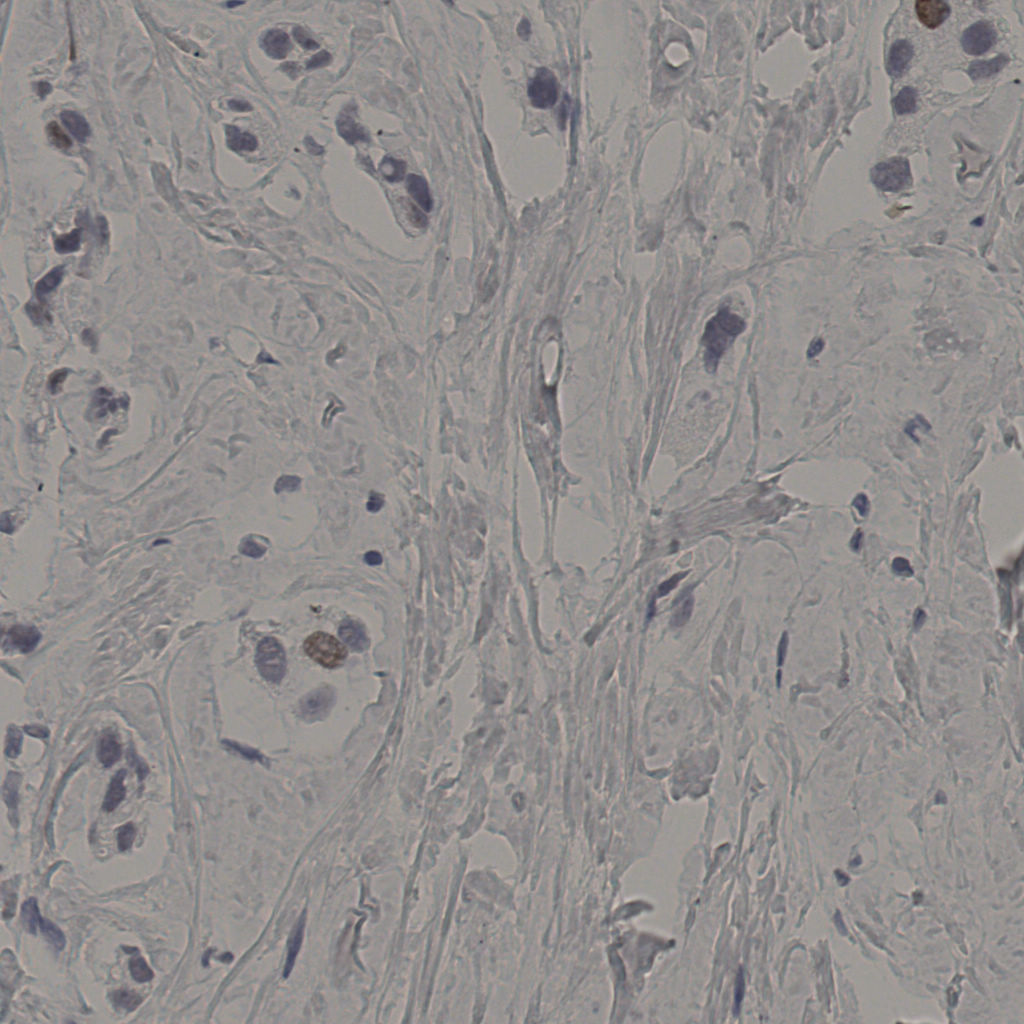

5.31%

Ki67 指数

阴 19502

阳 1093

切片统计

总切片

2970

有效

554

已标记

554

有效率

19%